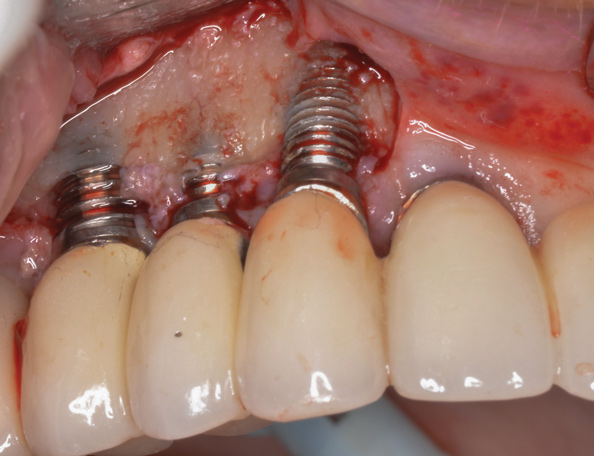

(4.) The implant in the molar position was relatively narrow and failed biomechanically. It was removed with a trephine, and the adjacent fractured bicuspid was also extracted to accommodate an implant. Because sufficient apical bone was present, a wider implant was placed in the molar position. Bone augmentation was performed around both implants.

Figure 4

(5.) The implant in the molar position was relatively narrow and failed biomechanically. It was removed with a trephine, and the adjacent fractured bicuspid was also extracted to accommodate an implant. Because sufficient apical bone was present, a wider implant was placed in the molar position. Bone augmentation was performed around both implants.

Figure 5